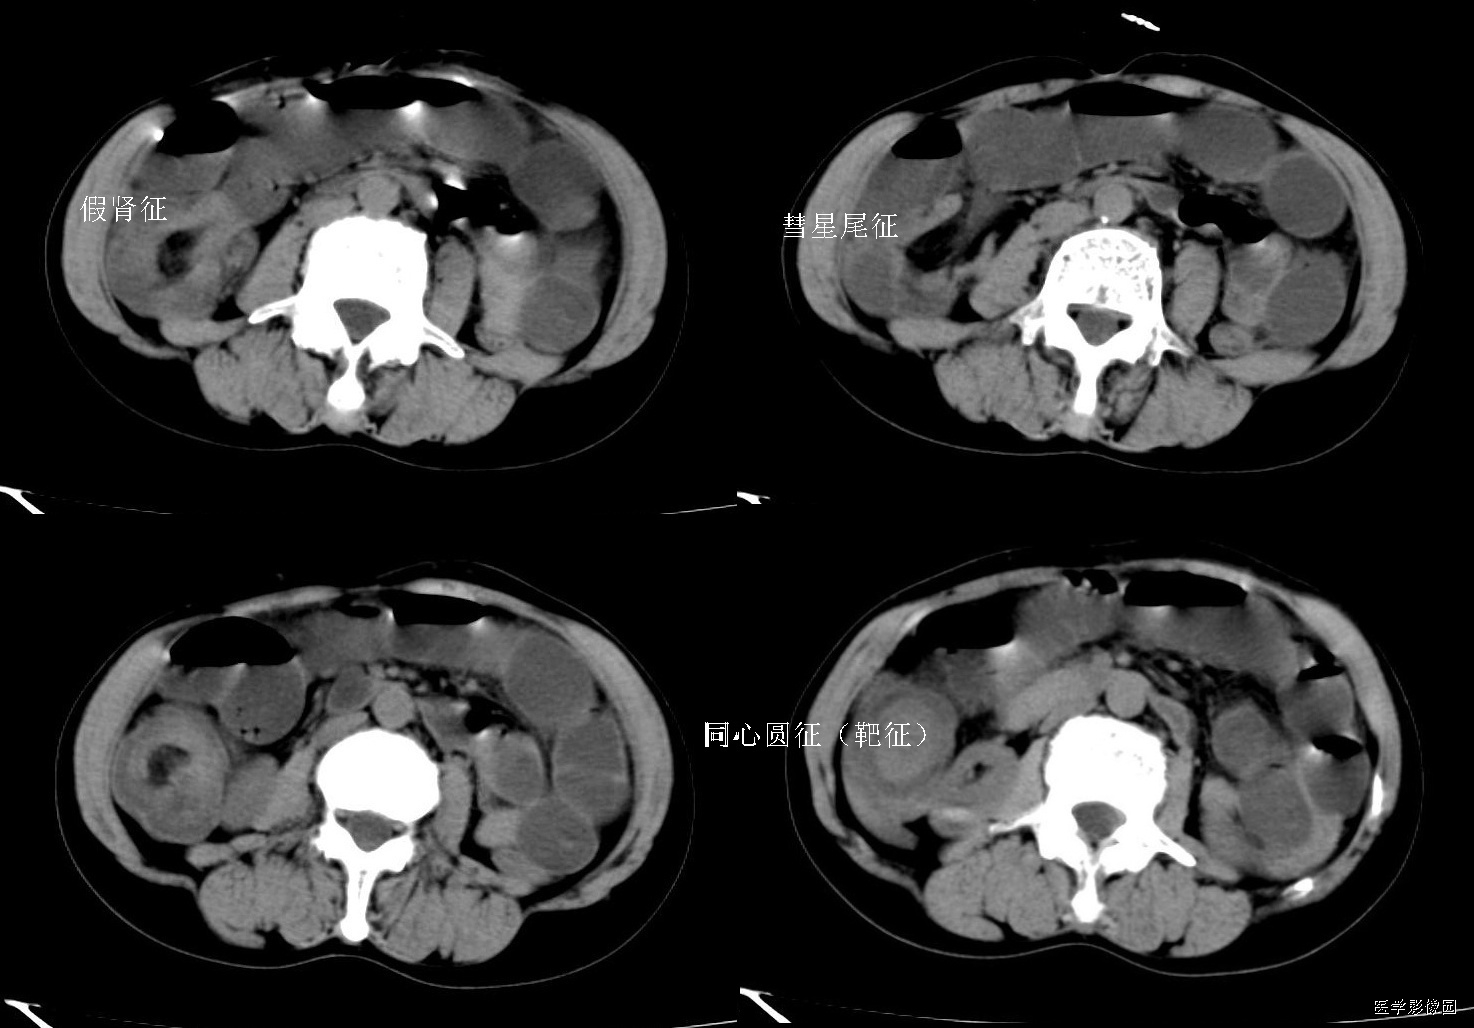

1、靶征(肠套叠)

是肠套叠最常见的特征性CT征像,为肠套叠长轴与CT扫描层面垂直时的表现,反映了套叠的各层肠壁、肠腔及肠系膜间的关系。典型排列为自外向内分别代表鞘部外层肠壁、鞘部肠腔内造影剂、鞘部内层肠壁、偏心性套入部肠系膜、套入部肠壁、套入部肠腔内造影剂。

如扫描层面和迂曲的肠道相平行时,表现为彗星尾征或肾形征:即套叠近端肠系膜血管牵拉聚拢的征象。一般情况下,慧星尾征均与肾型肿块相伴出现。该肾形肿块为套鞘部游离缘与套入部近端肠管及肠系膜的CT斜切面图像,其中游离的套鞘呈弧形围绕套入部,形状若肾轮廓外形,而套入部近端肠管、肠系膜形状若肾蒂。此时,所谓慧星尾征的组成还应包括套入近端肠管。如果套叠的肠管与CT扫描垂直,则呈靶形征,即肿块影表现为圆形或类似环形。通常在肿块内可分辨出层样结构,推测可能是继发于套入部和鞘部间的液体或是肠壁水肿造成密度对比,类似同心圆形;当套入部肠壁显著水肿坏死或套入部肿瘤周围浸润累及肠系膜,肠系膜血管及脂肪、套叠时间较长,套入部系膜血管受挤压时,静脉血液回流障碍,套入部肠壁充血水肿、变硬,形成不完全性肠梗阻,套叠以上肠管蠕动增强,可引起代偿性肠管扩张肥厚,并可见肠系膜连同其血管纠集、扭曲,形成“漩涡征”。